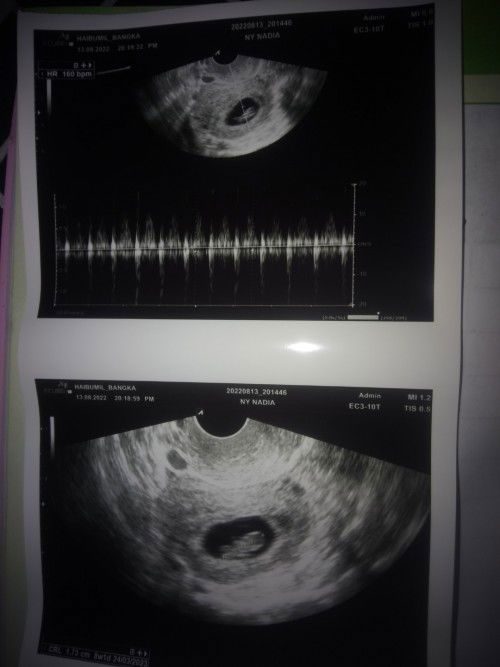

Saya baru pertama kali ini di suruh sesar krna posisi bayi sungsang, ada lilitan dn ketuban sedikit. Saya td di rujuk dari puskesmas ke RSUD. Usia kandungan 35 minggu 5 hari. Saya kira cm USG biasa. Tp sm dokter spesialis lngsg di jadwalkan sesar minggu depan. Yg bikin saya bingung, kondisi bayi saya itu bb baru 2,2kg lewat perkiraan USG. Dn setau saya jg itu blm cukup bulan untk lahir. Tp knpa saya lngsg di suruh sesar ya bund? Saya sdh tanya², katanya kalau bayi kecil harus segera di lahirkan. Itu berbanding terbalik dgn jawaban dokter spesialis di RS tipe B saat saya di rujuk krna kontraksi dn ada bukaan 1 saat usia 33 minggu. Jujur saya bingung bun, krna baru pertama kali sesar. Dulu 2x lahiran alhamdulillah normal. Jd saya butuh info dari bunda² yg tau atau sdh prnah sesar mngkn🙏#seriusnanya #bantusharing #ingintahu #pleasehelp